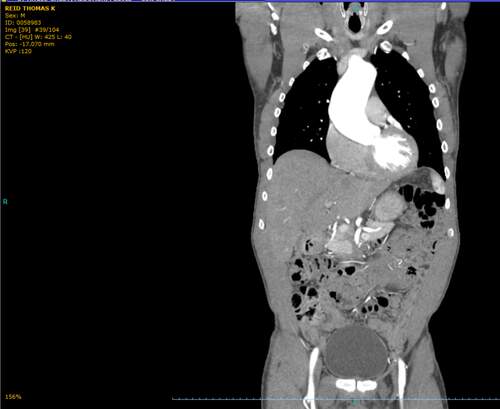

Arrived last night in NYC. Had my pre-op this a.m. I also met Dr. El-Hamamsy in person. I felt I already knew him from the Zoom meeting and watching all his video presentations on heartvalvesurgery.com as well as everything I could find on the internet. I am incredibly impressed by him. I am great at routine eye care and routine eye surgeries. I'm an excellent cataract surgeon. But those are so simple compared to cardio-thoracic surgery, aneurysm repair and Ross procedures. I am so thankful there are people like Dr. El-Hamamsy who are so driven to be the best and provide the best care for patients with incredibly difficult problems and to perfect their surgical technique to make this such a successful surgery. I know I'm in great hands for tomorrow!